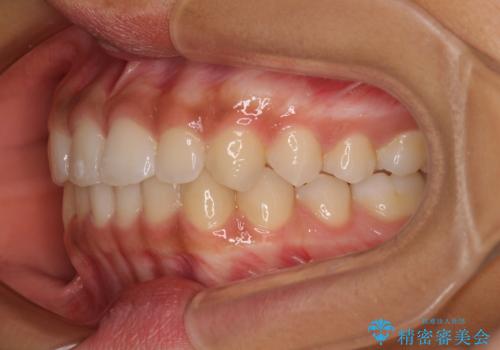

前歯のデコボコを治したい インビザライン・モデレートによる矯正治療

- 上下前歯の叢生を気にして来院された患者様です。

インビザラインでの治療を希望されていて、デコボコの程度が中等度であり、安価なパッケージにて対応可能と判断されたため、インビザライン・モデレートを用いて矯正治療を行うこととしました。